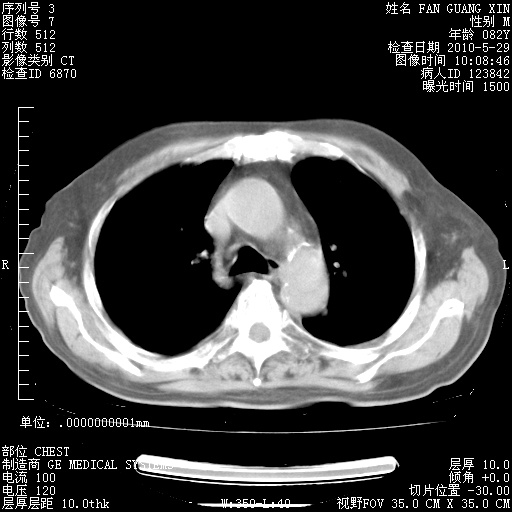

再治疗10天后的肺部CT 纵膈窗

从白细胞总数和中性比例看好像合并感染。肺部纹理好像比上次多,支气管炎?其他感染?

阅读此次胸部CT,肺间质渗出性改变较入院时有吸收。目前从体温、白细胞、中性分叶明显增高,肯定存在细菌感染(发生医院感染哦,若无消化道及泌尿系统等感染的依据,肺部感染可能大)。若你院头孢哌酮舒巴坦钠耐药率较高,同意你的方案,若48小时体温仍高,可考虑使用碳青霉稀类抗菌药物,同时可予超声雾化、注意滴数时加大液体量。白蛋白33.30g/L较低哦,需加强营养等支持治疗。